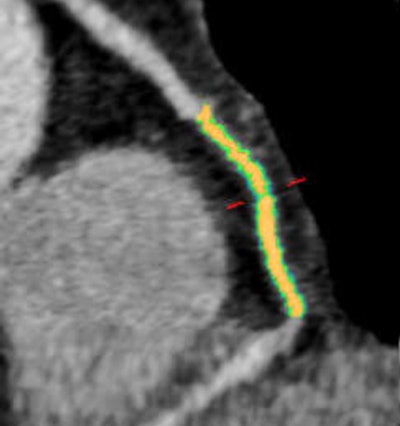

In all, 28 patients underwent coronary CT angiography on a dual-source CT scanner (Somatom Flash, Siemens Healthcare); however, the exclusion of patients who had stents or poor image quality left just 13 who underwent automated plaque analysis using an investigational software package (syngo.via Frontier, Siemens). Still, the results of plaque analysis showed a rather homogeneous pattern of culprit lesions in the mid right coronary artery (RCA).

Two experienced readers identified the culprit lesions in consensus, and plaque analysis was performed on a per-segment, per-vessel, and per-culprit-lesion basis. Culprit plaque composition was evaluated using mean attenuation thresholds, based on a 2012 meta-analysis:

"The software gives you the total volume of the segment, the volume of the lumen, and the volume of the plaques, and you can calculate the lumen narrowing in percentage," Mangold said.

Results of the per-vessel and per-segment analyses showed mean vessel lumen reductions of less than 50%. In all segments, the lipid-rich component comprised only 21% of plaque volume, while the most prevalent plaque component was fibrotic, at 71%.

The mean lumen reduction in the coronary arteries was only 23% in the overall evaluation, but lumen narrowing nearly doubled to 45% (p < 0.01) in the culprit lesions. The lipid component was also substantially higher, at 45%, compared with 21% in the overall analysis.